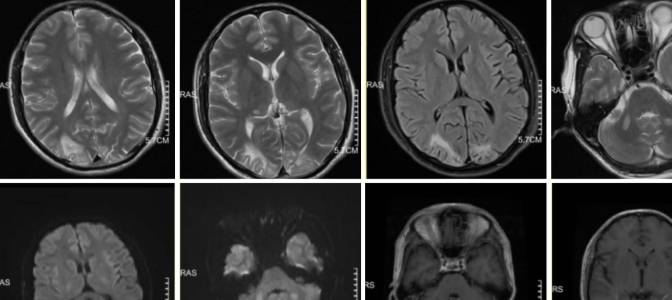

病例11

女性,71岁,因双下肢无力7天入院,既往高血压、心房颤动病史。

病例12

左侧肢体无力2天。

病例13

女,35岁,体检发现头颅MR异常。

病例14

男,50岁,因记忆力下降入院。